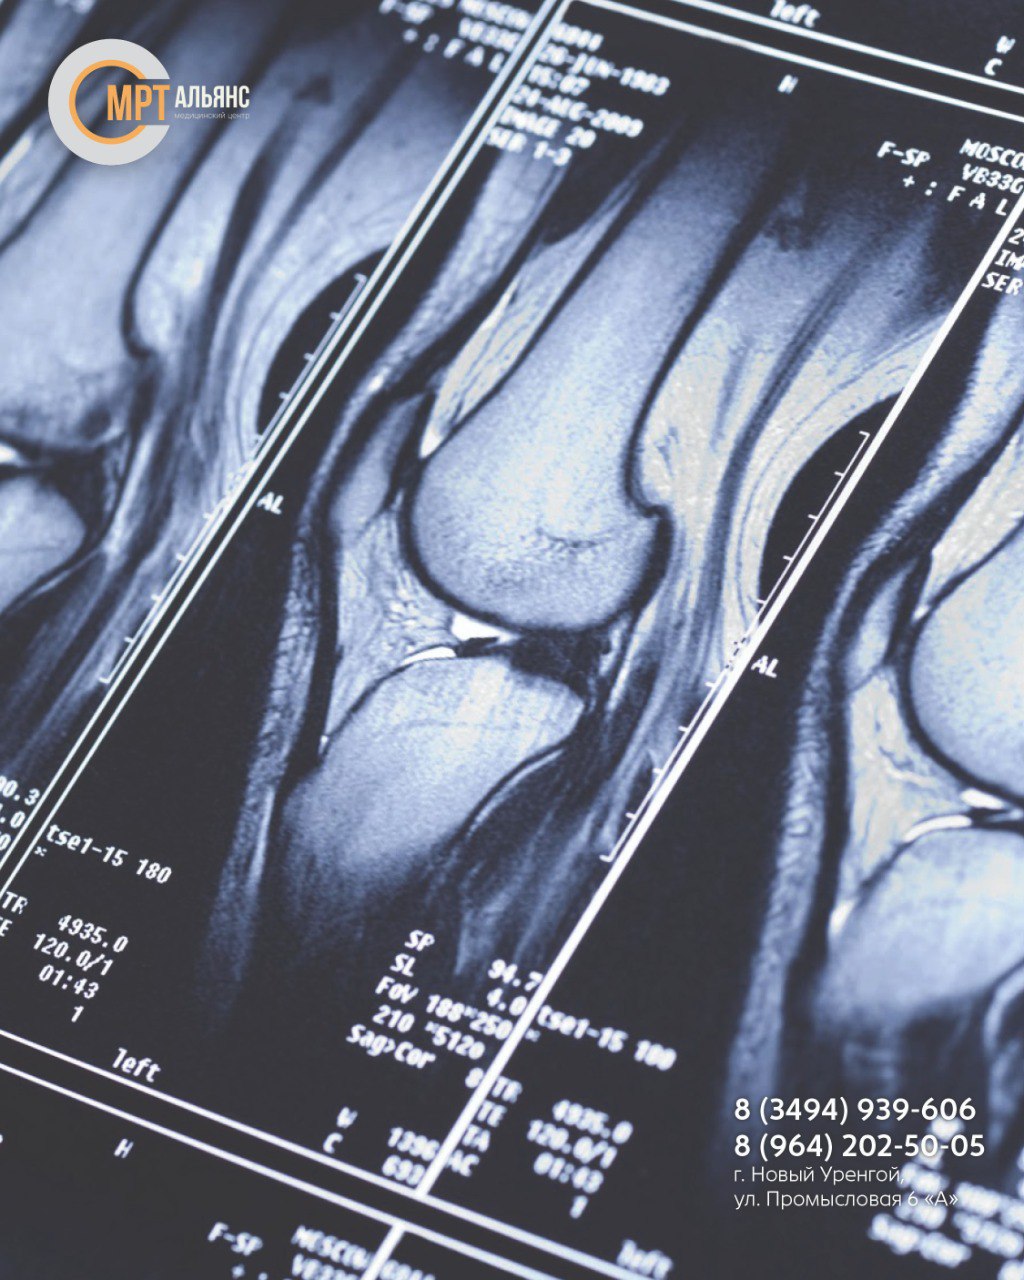

Магнитное поле проходит через исследуемую зону, отражается от анатомических структур сустава и возвращается в томограф. Датчики фиксируют интенсивность отраженных сигналов, на основе которых формируется высокоточное изображение тканей и суставных элементов

Показания к проведению МРТ колена:

• Врождённые аномалии и пороки развития

• Переломы, разрывы и растяжения связок

• Боли в колене неясного происхождения

• Подозрения на скопление жидкости в суставной сумке

• Признаки возрастных дегенеративных изменений

• Подозрения на опухолевые процессы

• Отёчность, покраснение кожи в области сустава

• Ограниченная подвижность

• Патологическая подвижность сустава

• Щелчки и хруст при ходьбе

Также применяется для подготовки к операциям, оценки результатов лечения и уточнения данных, полученных при рентгенографии или УЗИ

Преимущества метода:

• Безболезненность и безопасность для пациента

• Высокая информативность диагностики

• Получение детализированного изображения исследуемой зоны

• Отсутствие лучевой нагрузки

• Не требует специальной подготовки